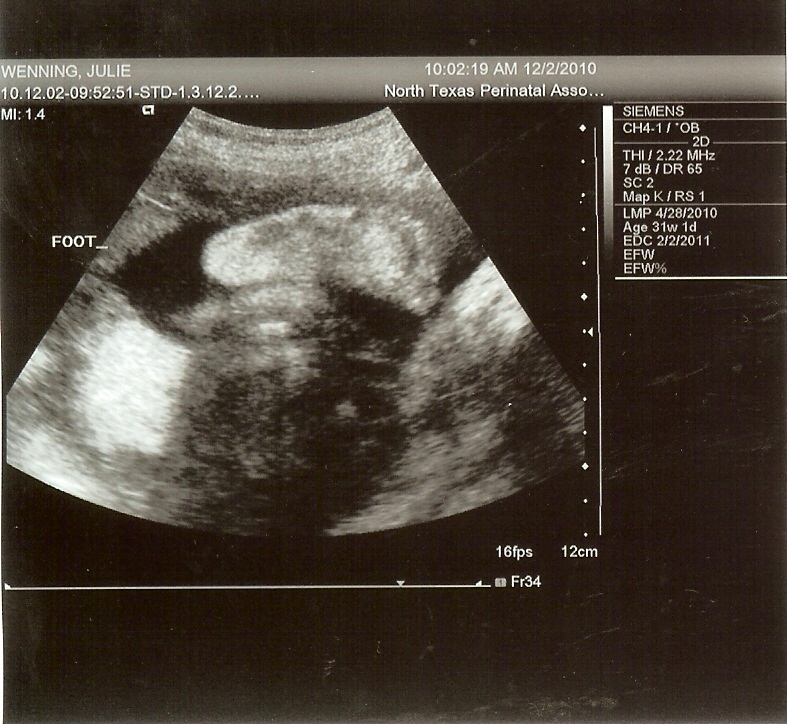

A precious little foot